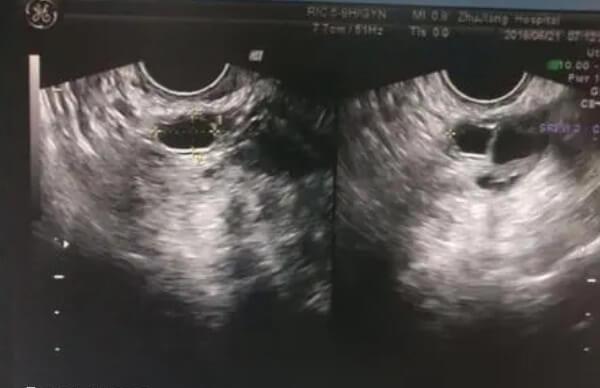

月经周期第12日起可以借助超声波技术观测卵泡其每日增长幅度在1.5-2毫米间。至第15或16日当成熟的卵泡直径达至20毫米时则会自然破裂并释放出卵子。卵泡的正常破裂通常发生在经期中间时段无任何明显异常症状,然而,部分女性可能出现短期的排卵痛或同侧腹部隐痛、排卵期出血等表现。